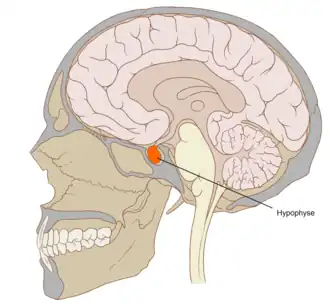

| Posição da glândula pituitária (ou hipófise) | |

A apoplexia pituitária é um enfarte ou uma hemorragia súbita da glândula pituitária, na presença dum adenoma pituitário. O sintoma inicial mais comum é uma súbita dor de cabeça, muitas vezes associada a um rápido agravamento do campo de visão e visão dupla causada pela compressão dos nervos que correm em estreita proximidade com a glândula. Normalmente, em muitos casos, pode-se constatar sintomas agudos causados por falta de secreção de hormonas essenciais, predominantemente insuficiência adrenal.[1]